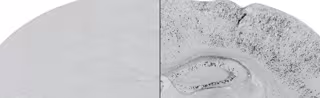

Acumulación experimental del fragmento de la proteína neurexina en el modelo animal (en negro, panel derecho), respecto a ratones control (panel izquierdo)

Acumulación experimental del fragmento de la proteína neurexina en el modelo animal (en negro, panel derecho), respecto a ratones control (panel izquierdo) - UNIVERSIDAD PABLO DE OLAVIDE

Los expertos han observado que su acumulación experimental en el cerebro adulto del modelo animal desencadena defectos específicos de memoria, entre otros. Estos modelos experimentales de enfermedad son importantes para la identificación de mecanismos patogénicos y fundamentales para el diseño de terapias efectivas.

Los científicos observan en estudios de comportamiento que la acumulación de dicha proteína produce una pérdida de memoria asociativa que depende de la amígdala del cerebro. En colaboración con el doctor José María Delgado se han estudiado las conexiones sinápticas de la corteza prefrontal a la amígdala mediante registros electrofisiológicos en ratones. Estos experimentos han mostrado que la acumulación de NrxnCTF produce también defectos en la plasticidad presináptica.